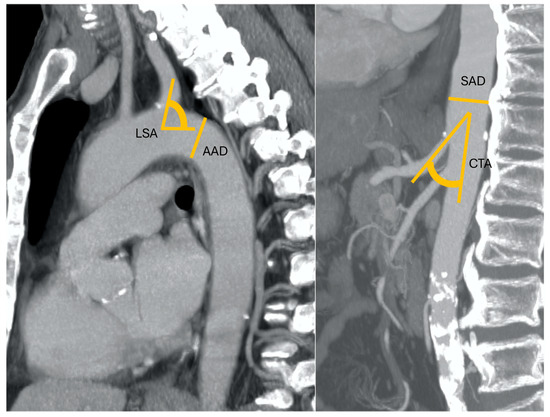

Figure 2. An 83-year-old patient with nodular HCC in the right liver lobe with a radial diameter (RD) of 2 mm (not shown) (0 points), left subclavian artery angle (LSA) of 45° (1 point), an aortic arch angulation (AAA) type III (1 point) with a diameter (AAD) of 32 mm (1 point), suprarenal aorta diameter (SAD) of 40 mm (1 point), and celiac trunk angle (CTA) of 130° (1 point). Final RAD-access score: 5, transfemoral access preferred for values between 3 and 6.